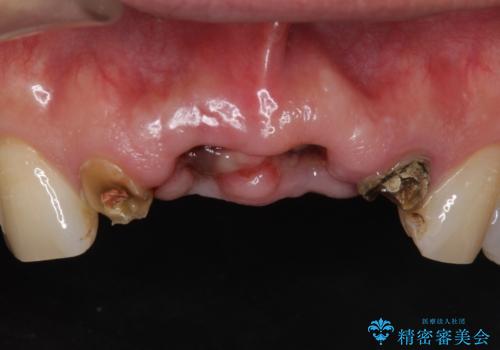

- お風呂場で転んで上の前歯が2本抜けてしまったことを主訴に来院された患者様です。

精査したところ、左上の側切歯(左上2)も破折しており保存不可能な状態でした。

左上の側切歯(左上2)を抜去し、右上の側切歯(右上2)の再根管治療後、セラミックのブリッジによる補綴を行いました。